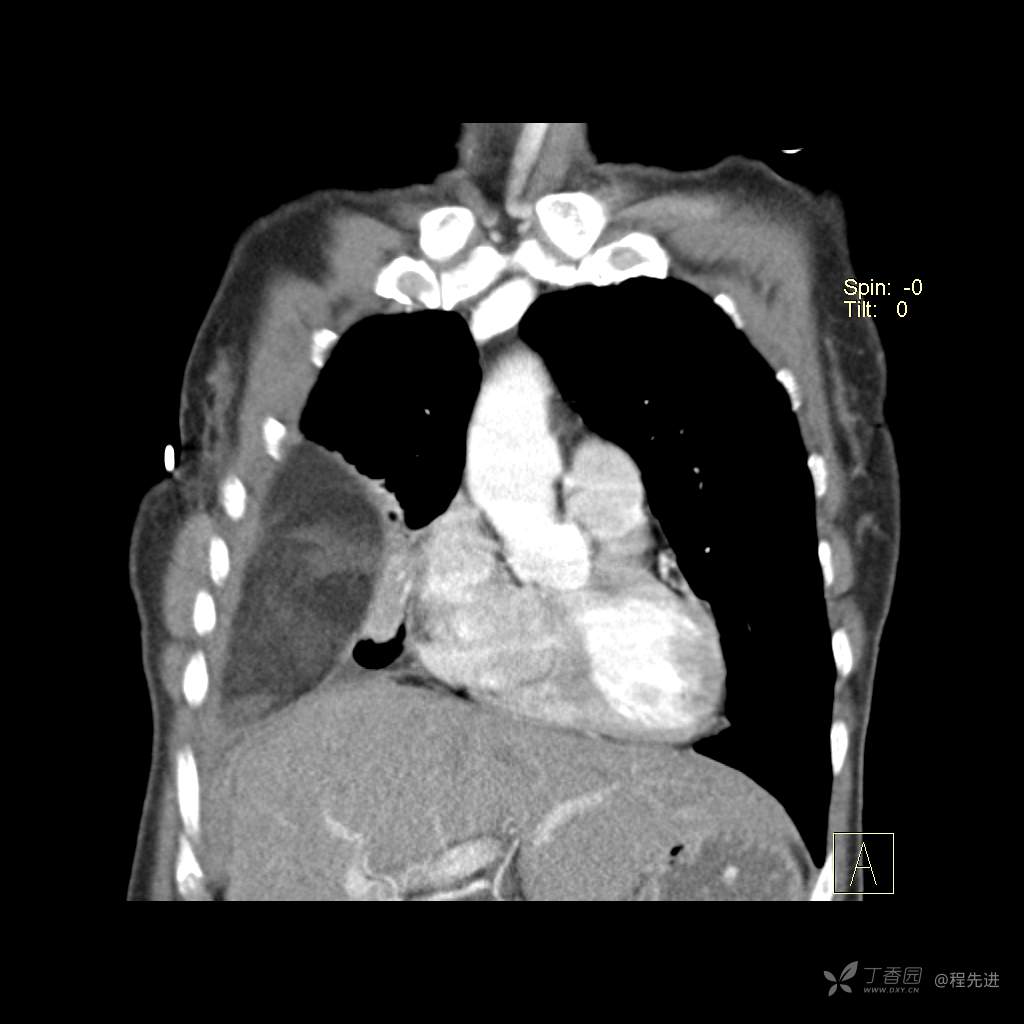

患者性别:女

患者年龄:51岁

简要病史:胸闷半年